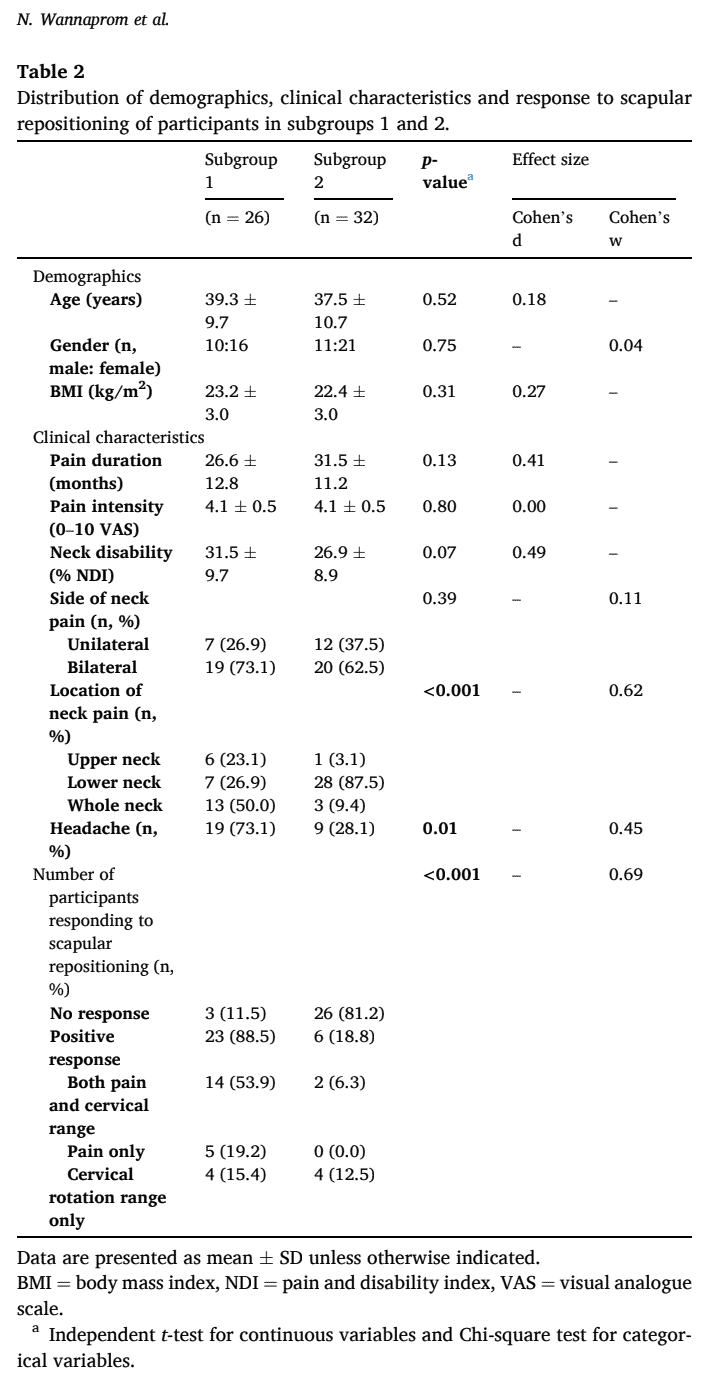

Trong nghiên cứu hiện tại, 58 người đã đồng ý tham gia. Trong số đó, 29 người đã có phản hồi vì trước đó họ đã trải nghiệm kết quả tích cực về tình trạng đau cổ và phạm vi chuyển động sau khi định vị lại xương bả vai. Có hai mươi chín người được phân loại là không phản hồi. Mẫu bao gồm khoảng 60% phụ nữ có độ tuổi trung bình là 38 (+/- 10 tuổi). Cường độ đau cổ của họ là 4,1 (+/- 0,5) theo thang điểm VAS và Chỉ số khuyết tật do đau cổ là 29,0 (+/- 9,4).

Hai nhóm nhỏ được xác định dựa trên phép đo 3D. Ở nhóm phụ 1, những người tham gia biểu hiện co xương đòn và xoay xương bả vai xuống dưới nhiều hơn. Ở nhóm phụ 2, độ cao của xương đòn tăng lên và xương bả vai nghiêng về phía trước nhiều hơn và xoay vào trong nhiều hơn. Nhóm 1 có báo cáo thường xuyên hơn về tình trạng đau đầu và đau nhiều hơn ở vùng cổ trên hoặc toàn bộ cổ, trong khi những người ở nhóm 2 báo cáo đau nhiều hơn ở vùng cổ dưới. Đối với tất cả các kết quả khác (nhân khẩu học, cường độ đau cổ, thời gian kéo dài và tình trạng khuyết tật), các nhóm con đều như nhau.

Xem xét phản ứng với việc thay đổi vị trí xương bả vai trong trường hợp đau cổ, nghiên cứu này phát hiện ra rằng 88,5% người tham gia trong nhóm phụ 1 phản ứng tích cực, trong khi 81,2% trong nhóm phụ 2 thì không.